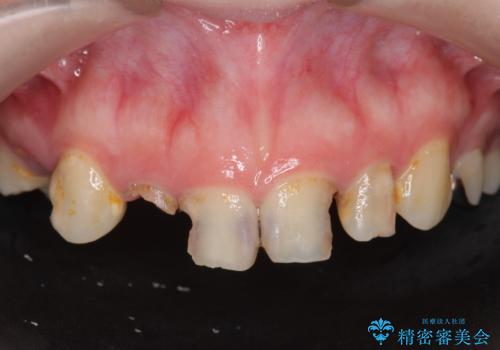

[ 歯肉縁下カリエス ] 歯周外科を行い、歯を残す

![[ 歯肉縁下カリエス ] 歯周外科を行い、歯を残すの症例 治療前](https://seimitsushinbi.jp/wp/wp-content/uploads/2023/01/9c47fe75d13e5b920ea2ccdb0dc8ed3b-500x350.jpg?v=1673602326)